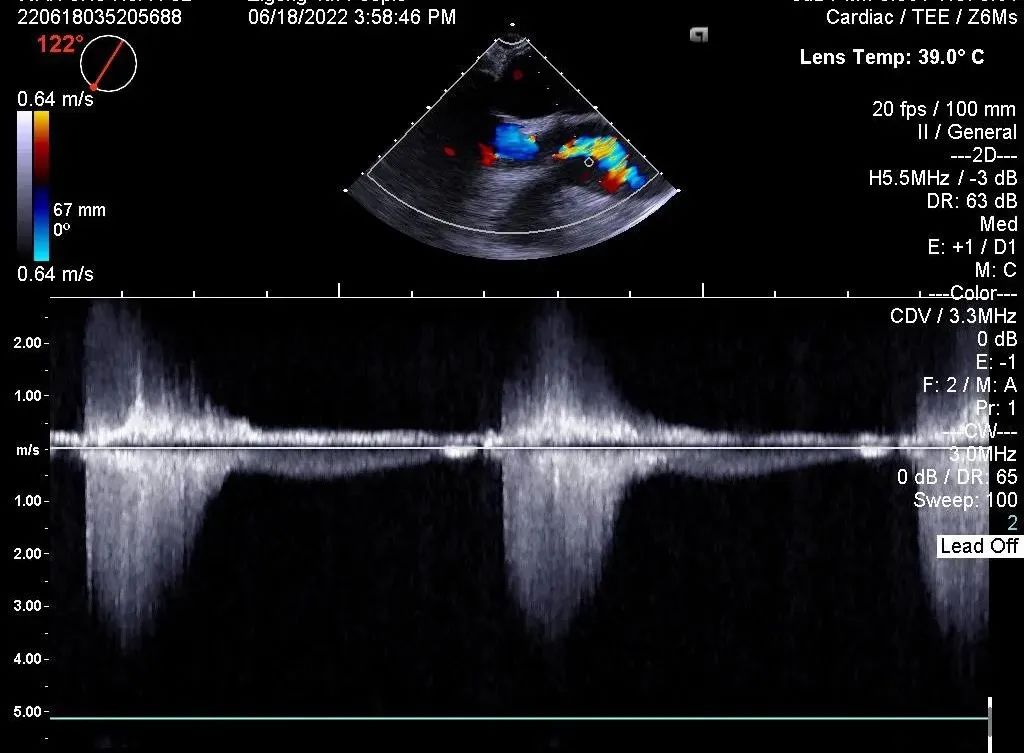

心脏彩超

• 主动脉瓣重度狭窄并关闭不全;

• 升主动脉增宽;

• 双房增大;

• 二、三尖瓣中度反流;

• 室间隔及左室后壁增厚;

• LVEF: 63%;

• 主动脉瓣瓣口最大流速:4.78m/s;平均跨瓣压差:53mmHg。

术后彩超:峰值流速2.34m/s,跨瓣压差8.8mmHg

在多学科协作下,自贡市第四人民医院心内科已完成多例经股动脉介入主动脉瓣置换术,经过2个小时紧张有序的操作,本次手术亦取得圆满成功。术后,主动脉瓣人工瓣膜功能可,患者的平均跨瓣压差由术前的53mmHg,改善至术后的8.8mmHg, 峰值流速由术前的4.78m/s改善至术后的2.34m/s。患者获益明显, 且在苏醒后顺利转入病房,术后第2天便可下床正常活动。